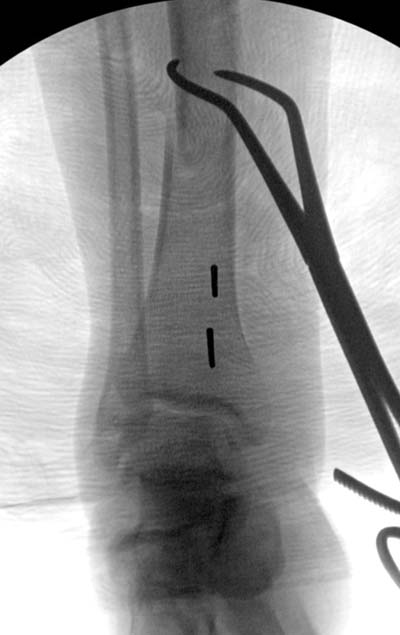

Здесь несколько снимков изолированного перелома большеберцовой с интактной малоберцовой. Weber clamp, блокирующие спицы и риминг в центре канала отрепонировал перелом....